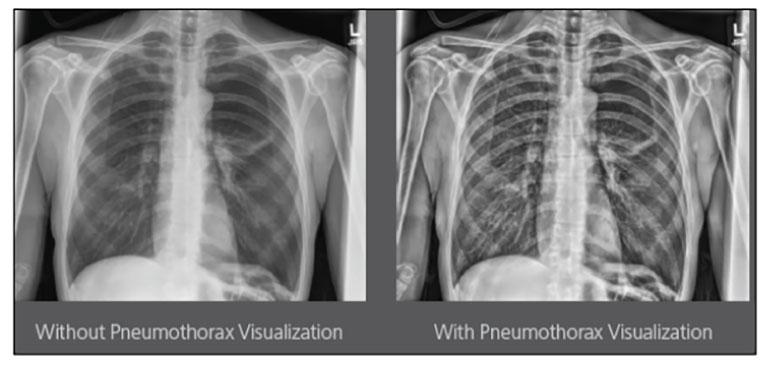

Carestream Introduces New Software Update to Boost Diagnostic Accuracy

Carestream today announced the latest update to its Image Suite V4 Software, MR 11: a series of enhancements to help improve customer confidence and increase diagnostic accuracy [...]

CARESTREAM Image Suite V4 MR11 has set a new standard for workflow efficiency, offering a robust set of features and functionalities to enhance clinical confidence in healthcare professionals. Using an auto-generated companion image from a single exposure, leverage a range of image processing options to increase diagnostic accuracy and enhance patient care.